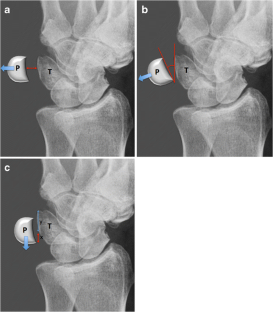

Fig. 3